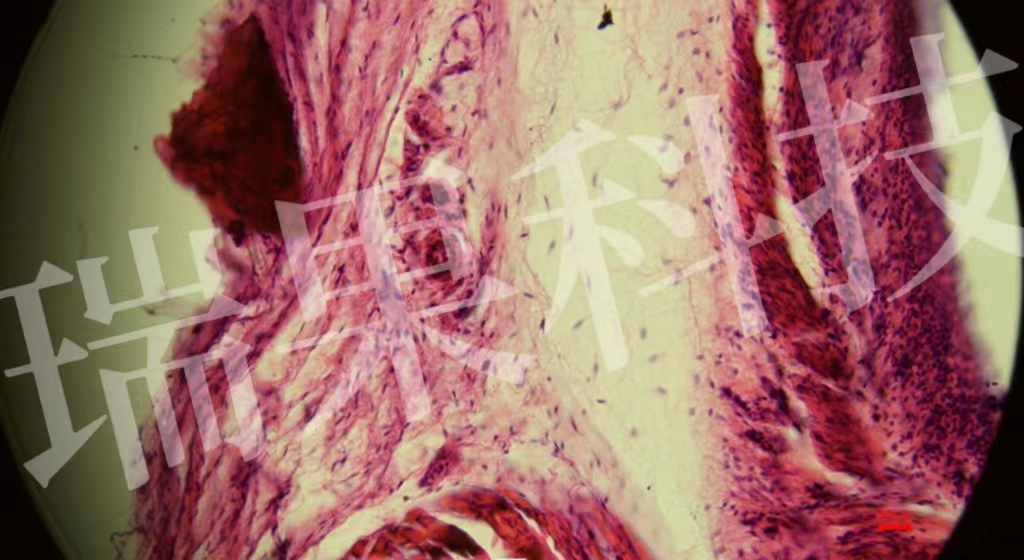

HE染色:苏木精 - 伊红染色法 ( hematoxylin-eosin staining ) ,简称HE染色法 ,石蜡切片技术里常用的染色法之一 。苏木精染液为碱性 ,主要使细胞核内的染色质与胞质内的核酸着紫蓝色 ;伊红为酸性染料 ,主要使细

HE染色:苏木精 - 伊红染色法 ( hematoxylin-eosin staining ) ,简称HE染色法 ,石蜡切片技术里常用的染色法之一 。染液为碱性 ,主要使细胞核内的染色质与胞质内的核酸着紫蓝色 ;伊红为酸性染料 ,主要使细胞质和中的成分着红色 。HE染色法是组织学、、病理学教学与科研中最基本、使用最广泛的技术方法。